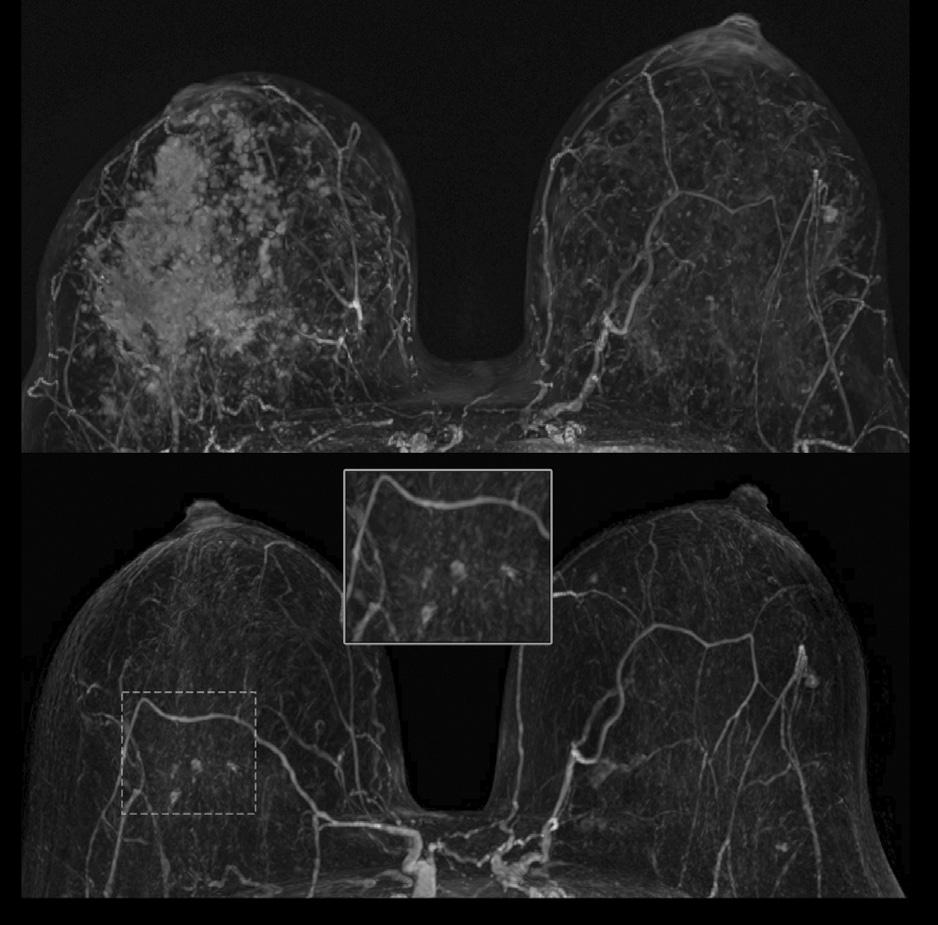

Morfologisk ses også ulike responsmønstre. Konsentrisk skrumpning er typisk for trippel-negativ og HER2-positiv brystkreft. Spredt respons er vanligere ved hormonreseptor-positive tumorer, spesielt lobulær brystkreft, noe som kan komplisere kirurgisk planlegging (9). (Graf 1) (Bilde 2)

BILDE 2: MR bilder før og etter neoadjuvant systemisk behandling med komplett radiologisk respons.

BILDE 3: MR-bilder før og etter neoadjuvant systemisk behandling med spredt radiologisk responsmønster.